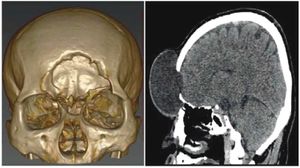

Publication: Int J Comput Assist Radiol Surg. 2016 Mar;11(3):473-81. PMID: 26183148 Authors: De Momi E, Ferrigno G, Bosoni G, Bassanini P, Blasi P, Casaceli G, Fuschillo D, Castana L, Cossu M, Lo Russo G, Cardinale F. Institution: Department of Electronics, Information and Bioengineering (DEIB), Politecnico di Milano, Milan, Italy. Background/Purpose: Image guidance is widely used in neurosurgery. Tracking systems (neuronavigators) allow registering the preoperative image space to the surgical space. The localization accuracy is influenced by technical and clinical factors, such as brain shift. This paper aims at providing quantitative measure of the time-varying brain shift during open epilepsy surgery, and at measuring the pattern of brain deformation with respect to three potentially meaningful parameters: craniotomy area, craniotomy orientation and gravity vector direction in the images reference frame. Methods: We integrated an image-guided surgery system with 3D Slicer, an open-source package freely available in the Internet. We identified the preoperative position of several cortical features in the image space of 12 patients, inspecting both the multiplanar and the 3D reconstructions. We subsequently repeatedly tracked their position in the surgical space. Therefore, we measured the cortical shift, following its time-related changes and estimating its correlation with gravity and craniotomy normal directions. Results: The mean of the median brain shift amount is 9.64 mm ([Formula: see text] mm). The brain shift amount resulted not correlated with respect to the gravity direction, the craniotomy normal, the angle between the gravity and the craniotomy normal and the craniotomy area. Conclusions:Our method, which relies on cortex surface 3D measurements, gave results, which are consistent with literature. Our measurements are useful for the neurosurgeon, since they provide a continuous monitoring of the intra-operative sinking or bulking of the brain, giving an estimate of the preoperative images validity versus time. |